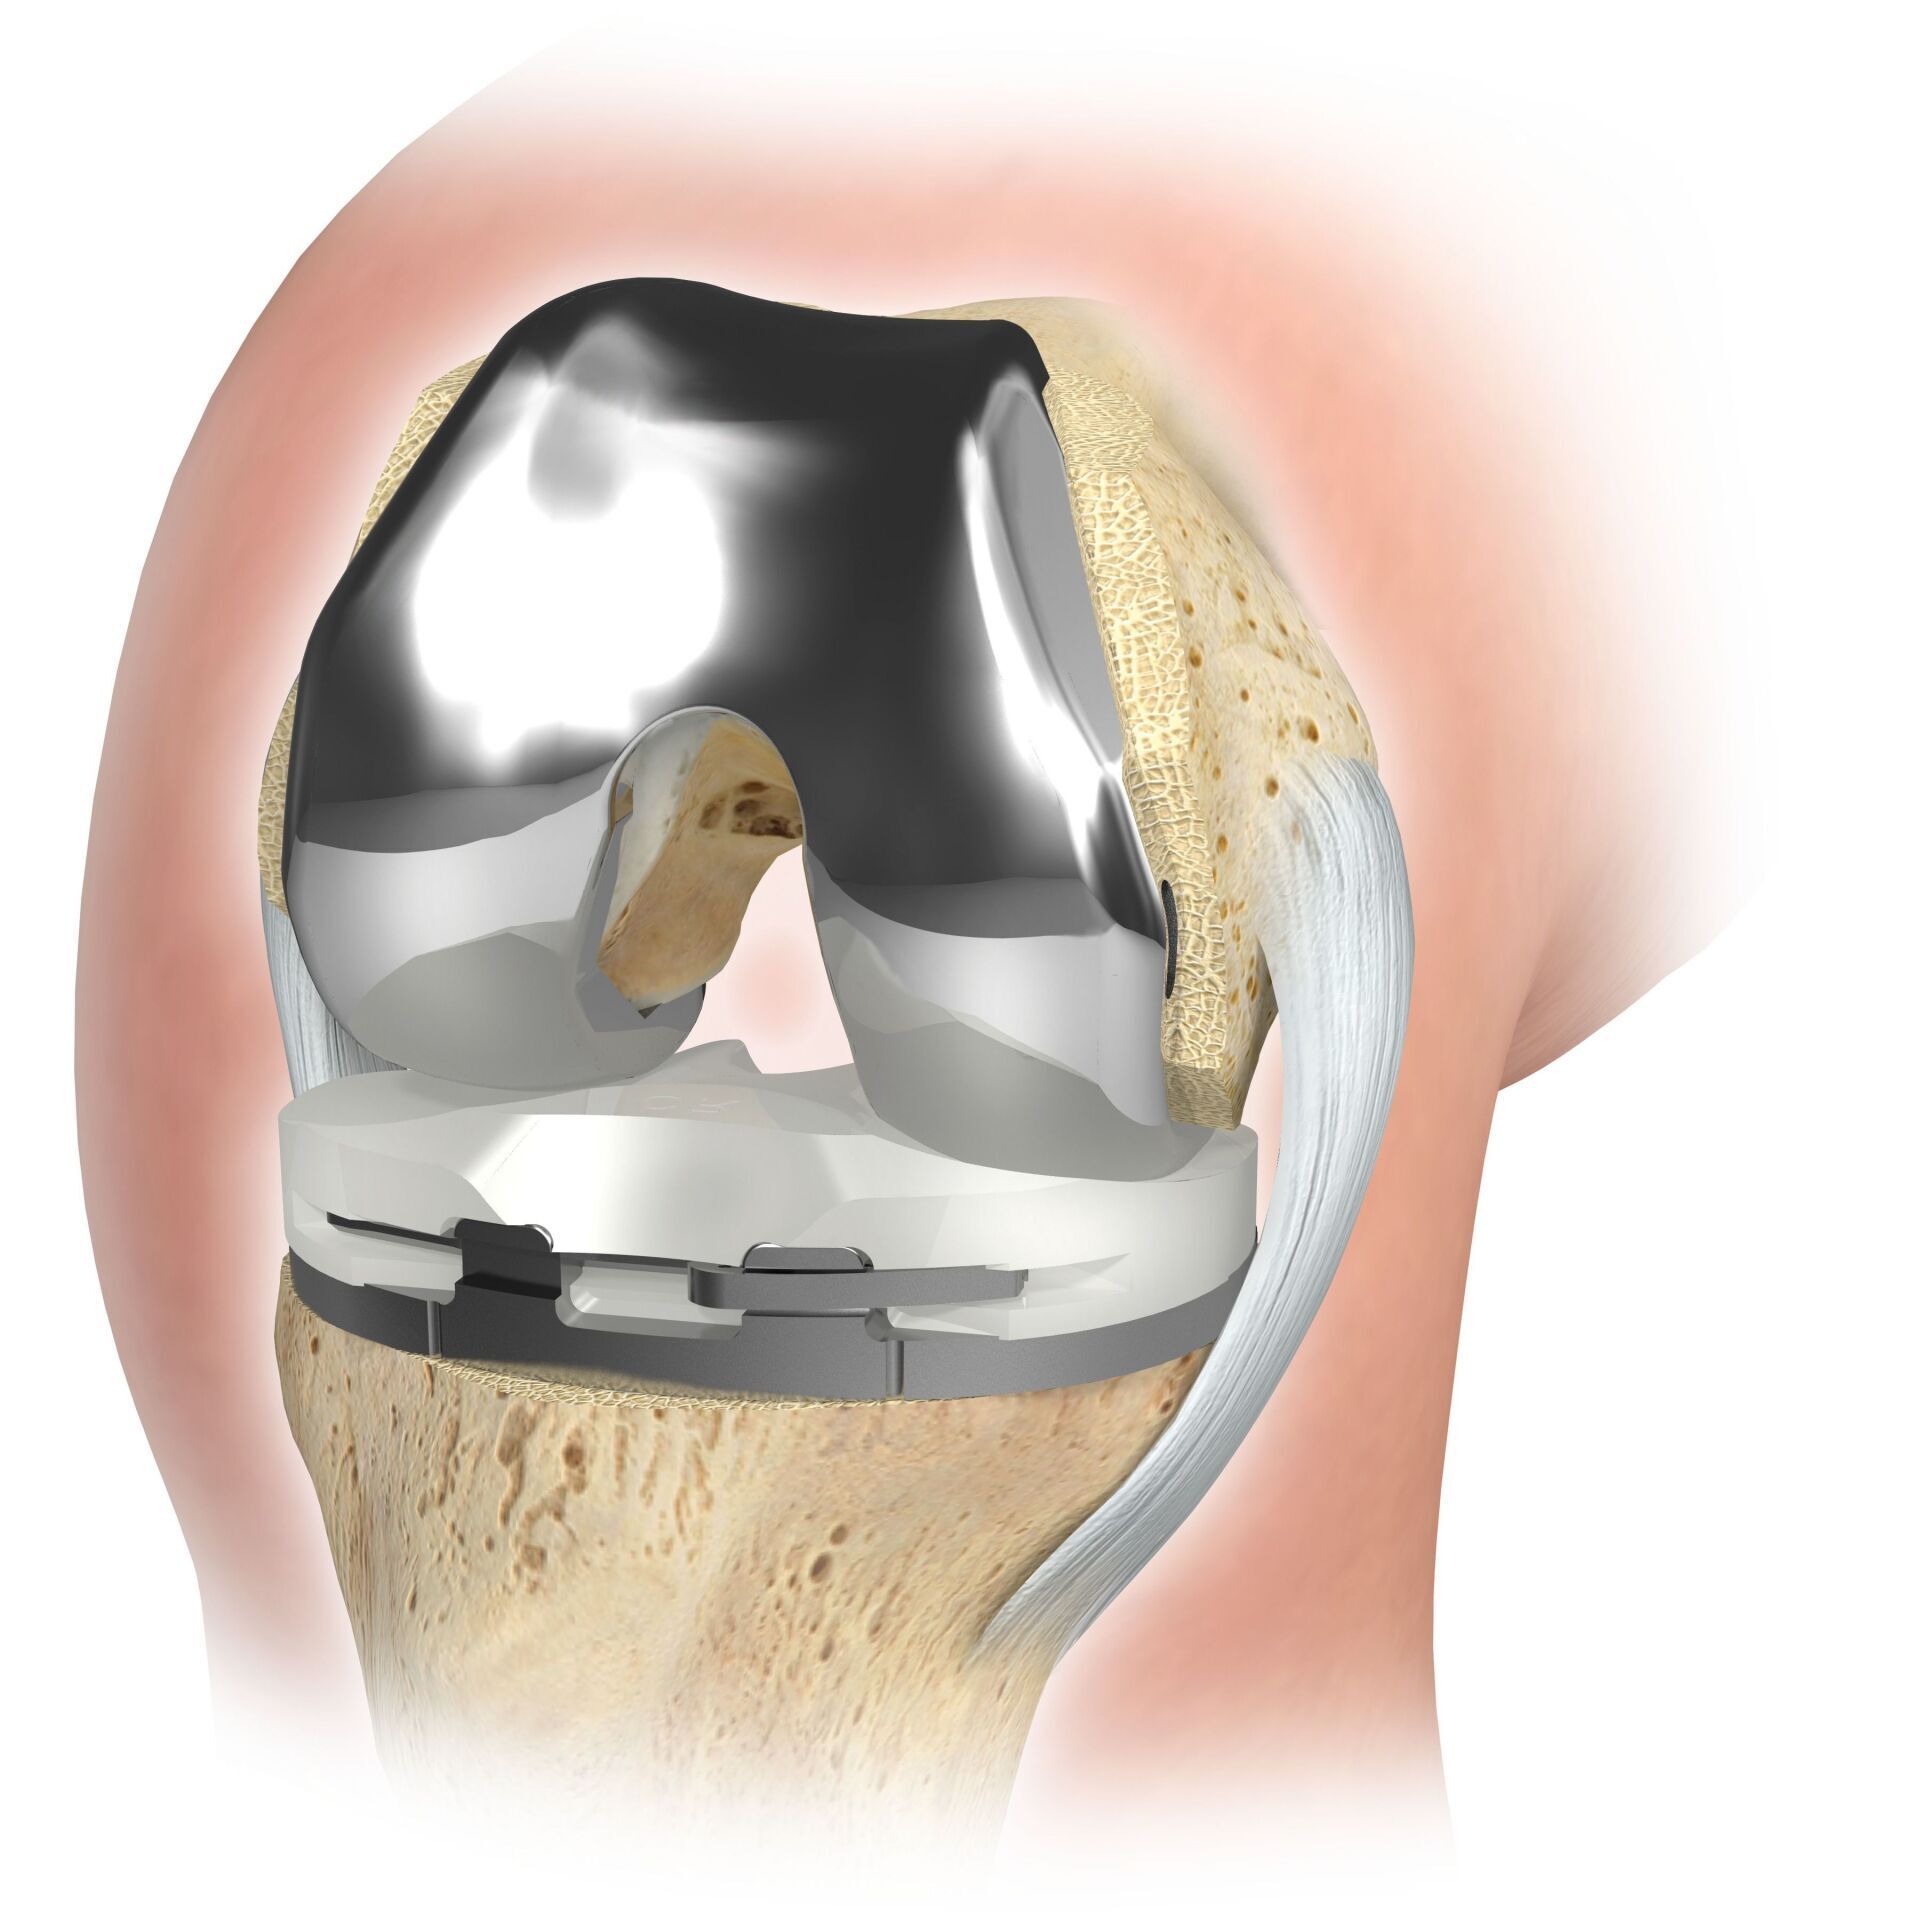

TKA (مفصل الركبة الاصطناعي)

يحل مفصل الركبة الاصطناعي محل سطح الغضروف الذي دمره التهاب المفاصل العظمي. يظل العظم الأساسي في عظم الفخذ والرأس الظنبوبي سليمًا. يقارن البعض مفصل الركبة الاصطناعي الحديث بتتويج الأسنان؛ والمصطلح الدقيق هو ما يسمى بإعادة تسطيح اللقمتين. بين الأسطح الجديدة في الجزء العلوي والسفلي من الساق يوجد ما يسمى بالبطانة المصنوعة من البلاستيك الأبيض المقوى خصيصًا، والتي يمكن رؤيتها في صورة الأشعة السينية على أنها المسافة بين الأجزاء المعدنية.